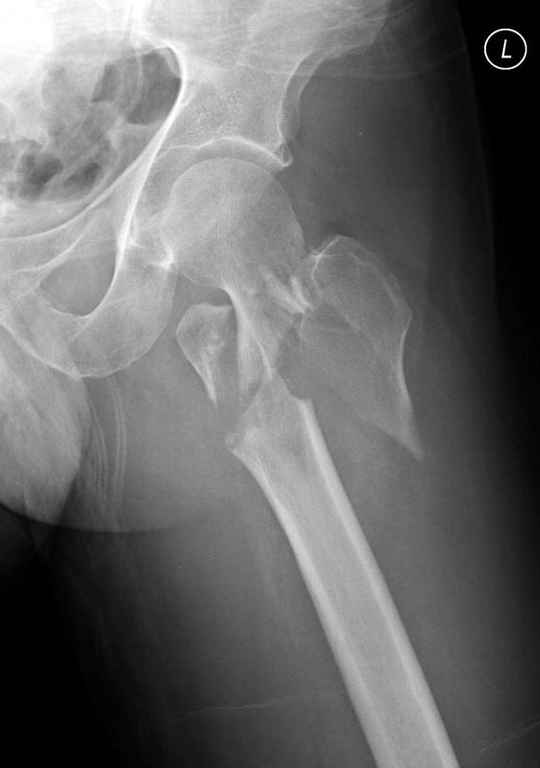

Re: оскольчатый чрезвертельный перелом

Предугадать распространение линий перелома при чрезвертельных и оскольчатых переломах трудно, поэтому для принятия правильного решения рекомендуется Компьютерно Томографические исследование.

При отсутствии КТ, снимок на вытяжении поможет увидеть общую картину расположения отломков, особенно потенциальные места введения импланта. Риск раскола в этом случае огромный, поэтому больной должен быть дообследован.

А так для лечения оскольчатых переломов подходят все методы, включая интра- и экстрамедуллярные в зависимости от опыта и наличия импланта.